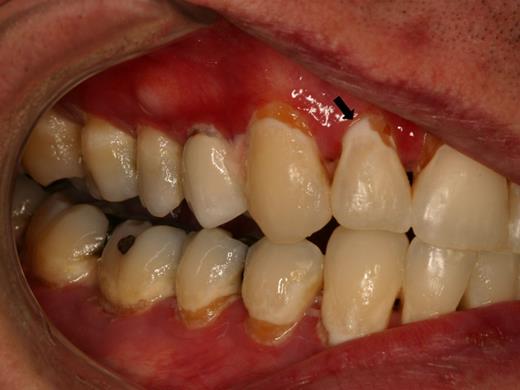

Patients with salivary gland cGVHD are at risk for developing secondary infectious complications because of diminished anticariogenic and antifungal activities. In addition to the effects on teeth (Figure 7), patients are at significant risk for recurrent oral candidiasis, especially if there is ongoing topical corticosteroid therapy for management of mucosal cGVHD, which suppresses mucosal immunity (see “Infections”; Figure 8).

Rampant cervical dental caries affecting all of the teeth in a patient with cGVHD of the salivary glands. Demineralization changes (arrow) appear chalky white.

Dental caries

Patients with salivary gland cGVHD are at risk for developing secondary infectious complications because of diminished anticariogenic and antifungal activities. The development of accelerated and often rampant dental caries is a largely under-recognized complication of oral cGVHD that can develop rapidly, leading to extensive dental treatment, extraction of teeth, and significant social and economic costs.65-67 Before the development of frank carious lesions, the teeth may demonstrate demineralization changes along the cervical margins, characterized by a white and chalky appearance (Figure 7). Dental caries tend to develop at the cervical margins and interproximal surfaces where dental plaque accumulates because of lack of salivary flow. Exacerbating this problem is that patients with oral mucosal cGVHD may neglect oral hygiene because of discomfort associated with tooth brushing, compounding the effects of salivary gland changes. In addition to the effects on teeth, patients with salivary gland cGVHD are at significant risk for recurrent oral candidiasis, especially if there is ongoing topical corticosteroid therapy.

Prevention of dental caries is a critical component of salivary gland cGVHD management, and we initiate these measures in all patients with clinically significant disease (Table 4). Patients should be continuously reminded of the importance of maintaining a noncariogenic diet and good oral hygiene. In patients with severe salivary gland hypofunction, even when tooth brushing after eating is not feasible, patients should be instructed to rinse their mouths well with water. Prescription 1.1% sodium fluoride gel should be applied to the teeth nightly, either using a toothbrush to “paint on” to the teeth, or via custom-fitting trays that can be fabricated by the patient's dentist.68,69 In addition to topical fluoride, emerging evidence supports the use of a calcium/phosphate-based remineralizing agent (eg, GC MI Paste Plus, GC America), which can be applied just before topical fluoride.70,71 Dentists can place fluoride varnish twice annually during recall visits for further protection. Bitewing radiographs should be obtained on an annual basis to screen for interproximal decay (Figure 15), and areas of decay should be treated promptly and definitively (ie, the full extent of caries must be removed as risk for recurrent decay is high).